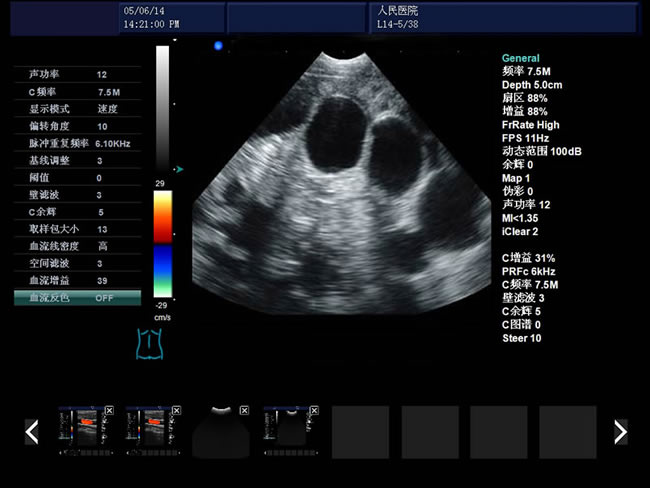

S9 彩色多普勒獸用超聲診斷儀

• S9彩色多普勒獸用超聲診斷儀是徐州市大為電子設備有限公司推出的一款全新的彩色超聲診斷儀器。

• 臨床應用